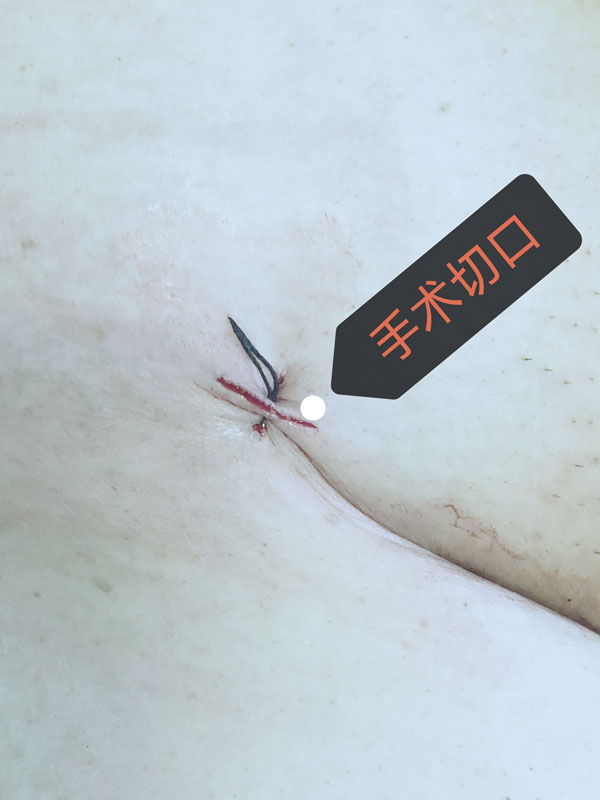

近日,在麻醉科、手术室、心内科、导管室、超声科等多学科的积极配合下,我院心血管外科团队在DSA复合手术室顺利完成两台高难度经导管主动脉瓣膜替换术(TAVR手术),皮肤切口仅1cm左右,以最小的创伤挽救了两名危重患者。该术式是一种运用导管导丝的微创技术,作为外科主动脉瓣膜置换术、药物治疗后的第三种治疗模式,有着不开胸、创伤小、时间短、恢复快等诸多优势,为许多高龄或危重的主动脉瓣患者带来希望。

经过充分的术前准备,两台手术由心血管外科赵永波副主任主刀,赵伟超主治医师、侯五辉主治医师密切配合,选择经皮股动脉穿刺,预埋缝合器,术中反复造影,准确定位释放瓣膜,术后造影及超声提示人工瓣膜开启功能良好。为确保术中安全,体外循环小组全程保驾护航。患者生命体征平稳,术后一日均转出监护室。